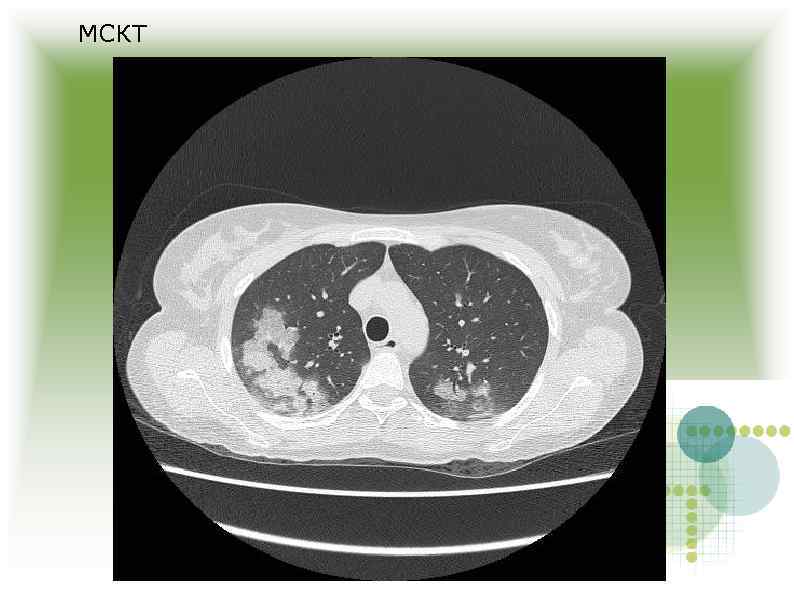

МСКТ МСКТ

Заключение МСКТ Признаки геморрагической пневмонии? Заключение МСКТ Признаки геморрагической пневмонии?